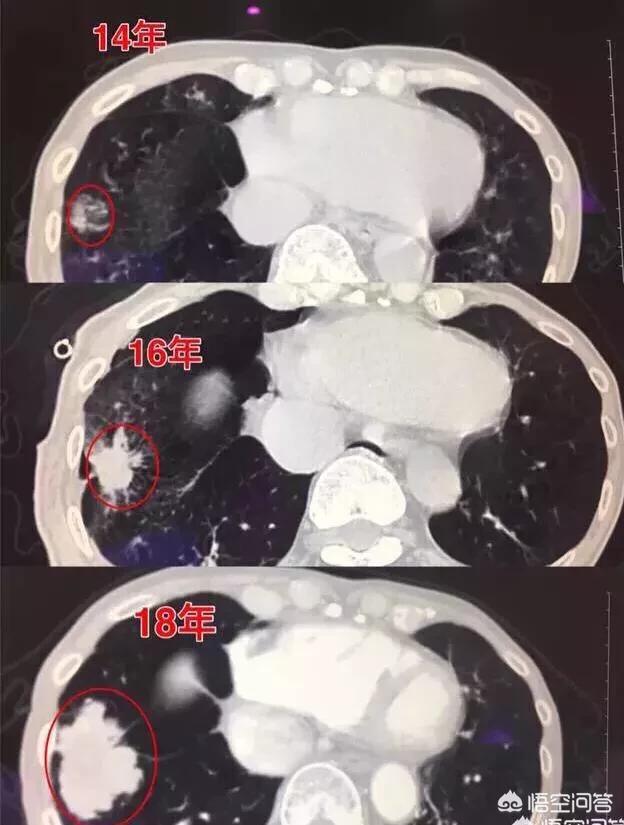

ちょうど2日前、私はある症例を読んだ。患者男性57歳、3年間の経過観察で、結節が0.5cmの大きさから肺がんになる過程を記録したばかりで、経過観察のたびに結節は大きくなっているが、患者は手術を選択しなかった。

矢印は結節を指しているが、2016年3月に発見されたときは約0.5cmと非常に小さかったが、今では定期検診でこのように非常に多くの結節が見つかっている。画像で良性か悪性かを判断する方法はなく、検討するという選択肢しかなく、検討と経過観察も最良の手段である。

7ヵ月後、2016年10月の2回目の経過観察では、この結節がより大きく、丸みを帯びていることが明らかになった。経過観察時の結節の拡大は悪性腫瘍の可能性を警告するものであったが、この患者はそれでも手術を選択しなかった。

さらに1年2カ月後、2017年12月に3回目の検査を受けた。この結節は以前よりずっと大きくなっており、悪性の徴候が小葉状に広がり、内部が固くなっているのがわかる。これらの徴候から、基本的に肺がんと診断されたが、それでも患者は手術を受けなかった。

結節は腫瘤(3cm以上)に変化しており、この肺がんは教科書的なもので、基本的に肺がんを支持する悪性腫瘍の兆候をすべて備えている。不規則な境界、小葉、バリ、胸膜の引きつれの徴候。

ありがたいことに、転移病変はまだ見られず、外科的切除も可能です。治療がまだ選択肢にないのであれば、1年後に再診に来れば、複数の転移性変化が期待できます。実際、2回目の再診では病変が大きくなっているのが見つかり、その時点で外科的切除を行うべきでしたが、基本的に再発も転移もありませんでした。病変が大きくなると、今度は血液中にがん細胞がある可能性があり、そうなると再発・転移のリスクが高くなります。

例えば、これは4年連続で観察したが、しこりは大きくなり続けていた。